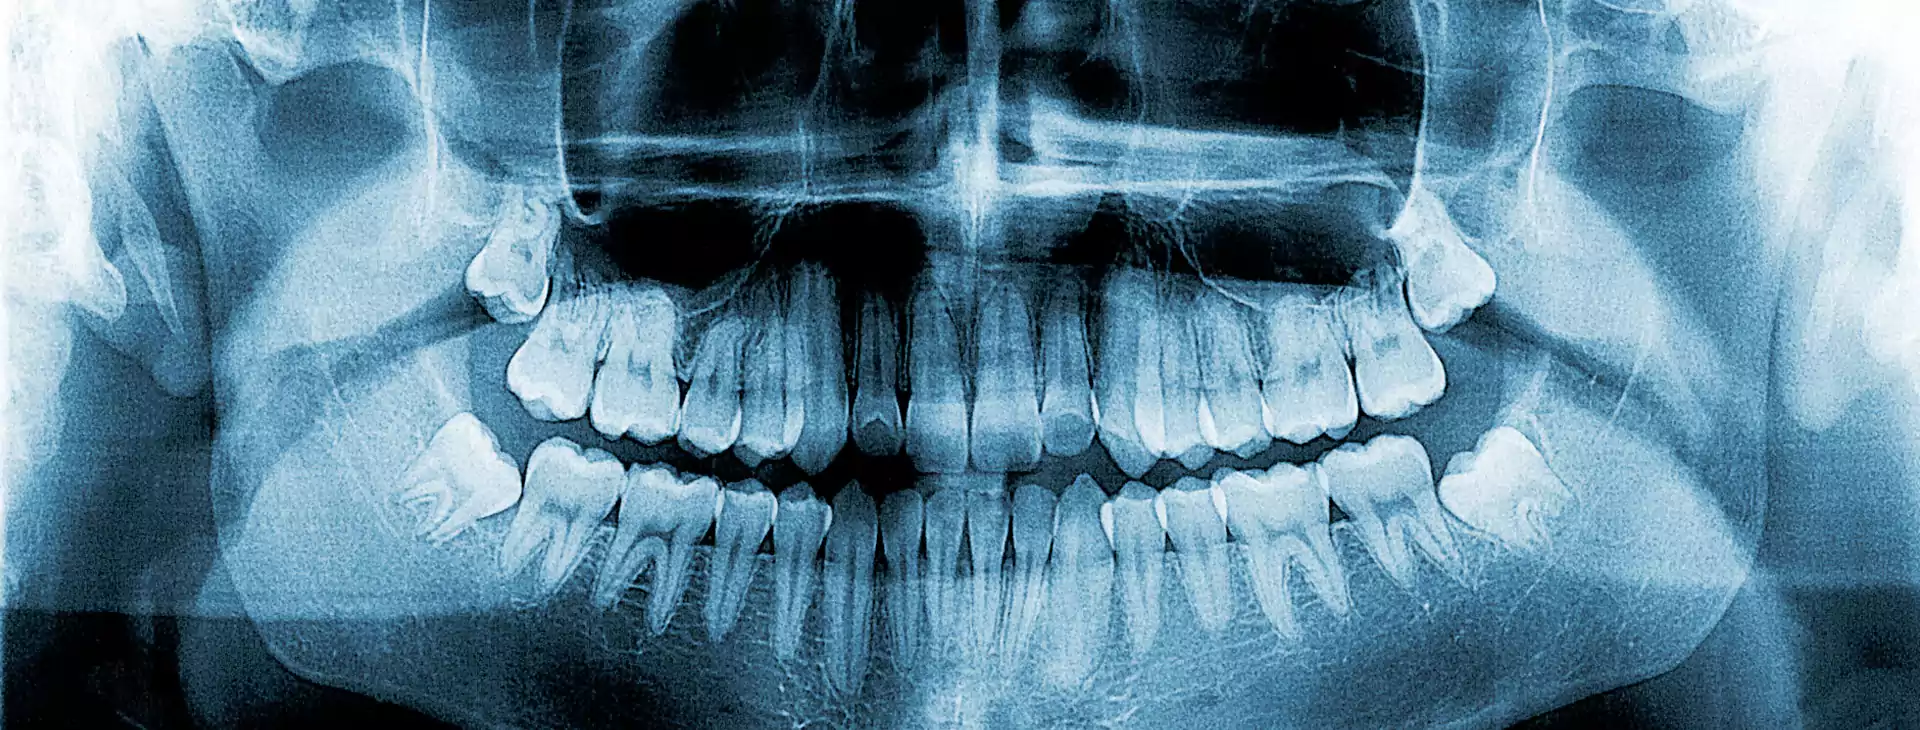

Expert Surgical Care for Complex Dental & Facial Conditions

At Balaji Dental Hospital, our Oral and Maxillofacial Surgery department offers specialized surgical solutions for complex dental, facial, and jaw-related conditions. Our expert surgeons combine precision, advanced techniques, and compassionate care to ensure the highest standards of treatment.

Wisdom Tooth Extractions (Impacted/Misaligned)

🔬 Advanced Surgical Equipment: High-precision tools and digital imaging for accurate diagnosis and minimal trauma